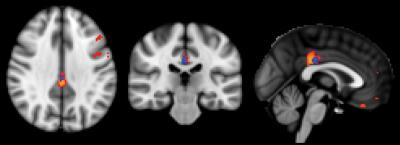

Of the 148 healthy individuals, 75 remained stable, while 73 deteriorated cognitively at 18 months clinical follow-up. Those who deteriorated had shown reduced perfusion at their baseline ASL MRI exams, particularly in the posterior cingulate cortex, an area in the middle of the brain that is associated with the default mode network, the neural network that is active when the brain is not concentrating on a specific task. Declines in this network are seen in MCI patients and are more pronounced in those with Alzheimer's disease.

The pattern of reduced perfusion in the brains of healthy individuals who went on to develop cognitive deficits was similar to that of patients with MCI.

"There is a known close link between neural activity and brain perfusion in the posterior cingulate cortex," Dr. Haller said. "Less perfusion indicates decreased neural activity."